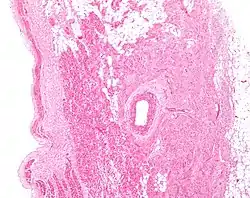

Figure 2: Low magnification stained image of the SA node (center-right on image) and its surrounding tissue. The SA node surrounds the sinoatrial nodal artery, seen as the open lumen. Cardiac muscle cells of the right atrium can be seen to the left of the node, and fat tissue to the right.

The cells of the SA node are spread out within a mesh of connective tissue, containing nerves, blood vessels, collagen and fat. Immediately surrounding the SA node cells are paranodal cells.[2] These cells have structures intermediate between that of the SA node cells and the rest of the atrium.[6] The connective tissue, along with the paranodal cells, insulate the SA node from the rest of the atrium, preventing the electrical activity of the atrial cells from affecting the SA node cells.[2] The SA node cells are smaller and paler than the surrounding atrial cells, with the average cell being around 8 micrometers in diameter and 20-30 micrometers in length (1 micrometer= 0.000001 meter).[7] Unlike the atrial cells, SA node cells contain fewer mitochondria and myofibers, as well as a smaller sarcoplasmic reticulum. This means that the SA node cells are less equipped to contract compared to the atrial and ventricular cells.[8]